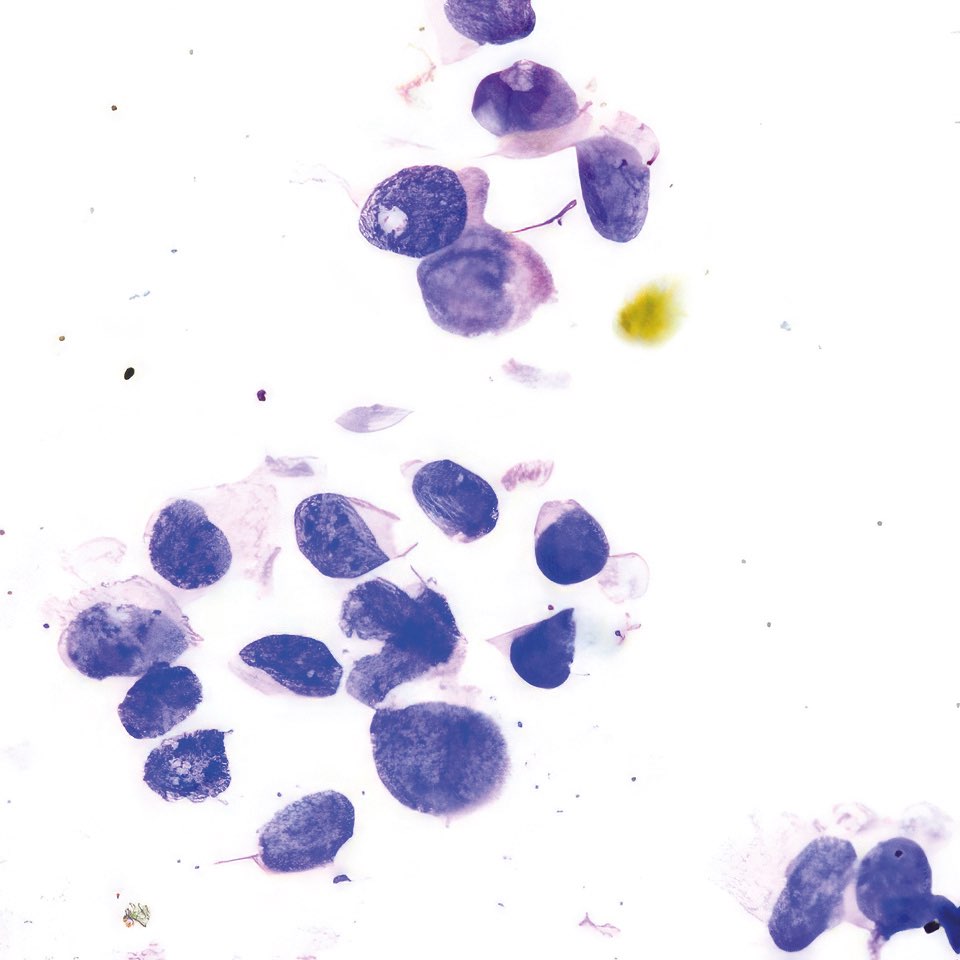

Abbildung 1 – 4: HE-Färbung; 1 – 4, original Obj. 40x, Abb. 4:

zusätzlich vergrößert

Die sich teils überlagernden Zellen erscheinen meist nacktkernig oder haben nur wenig Zytoplasma. Die Kerne variieren deutlich in Form und Größe, sind grob strukturiert und zeigen vereinzelt kleine Chromozentren und Protrusionen. Im Hintergrund etwas Zelldetritus.

Die histologischen Bilder (Abb. 1 und 2) bestätigen die zytologische Diagnose. Weite Teile des Gewebes sind durchsetzt von Tumorzellen, die nur angedeutet Verbände bilden und deutlich polymorphe Kerne aufweisen.

In diesem Fall bestand schon bei der klinischen Untersuchung kein Zweifel an der Karzinomdiagnose wegen eingezogener Brustwarze, oranger Hautfärbung und vergrößertem axillärem Lymphknoten, was klinisch nach WHO-Klassifikation T4bN1 entspricht. Die zytologische Diagnose eines Mammakarzinoms ist nicht immer so einfach. Dies gilt vor allem für das gut differenzierte tubuläre Karzinom, bei dem Größe und Form der Zellen nur schwer von normalen Zellen zu unterscheiden sind 12. Ähnliches gilt für das lobuläre Karzinom, dessen Zellkerne auch nur wenig in Form und Größe variieren; das auffälligste zytologische Merkmal ist die auch im zytologischen Präparat teilweise nachweisbare Indianfile-artige Anordnung 3. Die Trefferquote professionell durchgeführter FNA liegt knapp über 90%. Mag auch die Trefferquote der Dicknadel-Biopsie noch um wenige Prozent höher sein 4, so bietet die FNA besonders in unterversorgten Ländern den Vorteil, dass die Herstellung der Präparate einfacher, billiger und weniger zeitaufwendig ist.

Abbildung 1 und 2: Histologische Bilder desselben Falles, HE-Färbung, Abb.1: Obj. 10x, Abb. 2: Obj. 20x